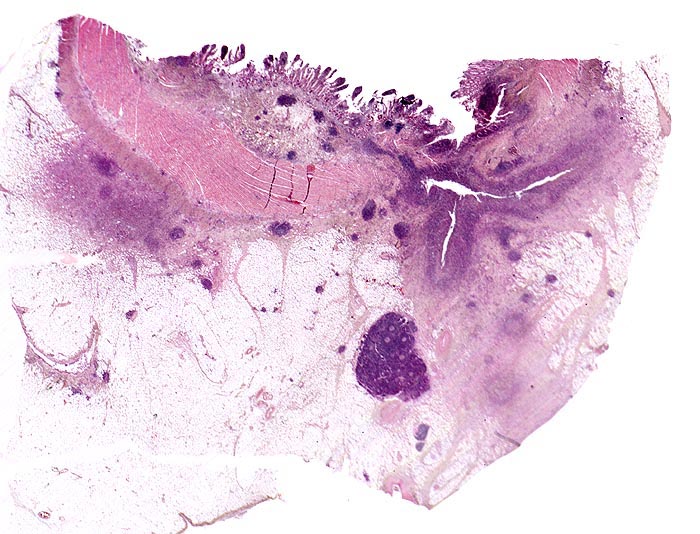

Die Verteilung der Läsionen im Darm ist sowohl makrokopisch (> 2884) als auch mikroskopisch (> 656) (> 409) diskontinuierlich und herdförmig ausgeprägt. Im Gegensatz zur Colitis ulcerosa können beim Morbus Crohn nicht nur das Kolon, sondern sämtliche Abschnitte des Gastrointestinaltraktes befallen sein. Am häufigsten ist das terminale Ileum zusammen mit dem Kolon befallen.

Makroskopisch typisch sind oberflächliche aphthöse Ulzera, gartenschlauchartige Strikturen im Dünn- und Dickdarm mit segmental verdickter und fibrosierter Darmwand, intramurale Abszesse, entzündliche Konglomerattumoren und verbackene Darmschlingen mit Fistelbildungen. Häufiger im Dünndarm als im Dickdarm findet sich das klassiche Pflastersteinrelief der Schleimhaut aufgrund rissförmiger Ulzera zwischen ödematösen Schleimhautarealen (> 369) Granulationsgewebspolypen oder Pseudopolypen (erhaltene Schleimhautinseln in Ulkusarealen) (> 408) finden sich beim Crohn seltener als bei der Colitis ulcerosa.

In Biopsien der Darmschleimhaut zeigen sich als Zeichen der Chronizität eine Architekturstörung, reepithelialisierte Schleimhautdefekte und metaplastische Veränderungen. Typisch für den Morbus Crohn sind entzündlich veränderte Schleimhautabschnitte neben weitgehend normaler Schleimhaut. In der Lamina propria findet sich ein verdichtetes gemischtes Infiltrat bestehend aus Lymphozyten, Plasmazellen, Makrophagen, neutrophilen und eosinophilen Granulozyten. Typisch für chronisch entzündliche Darmerkrankungen ist eine basal betonte Lymphoplasmozytose der Lamina propria. Die neutrophilen Granulozyten finden sich herdförmig in der Lamina propria, im Kryptenepithel (Kryptitis) und als Ansammlung in dilatierten Krypten (Kryptenabszess). Erhaltene Schleimhautabschnitte zwischen ulzerierten Arealen und Granulationsgewebe imponieren als entzündliche Pseudopolypen.

Befunde in der Mukosa wie epitheloidzellige Granulome, aphthöse Ulzera und Erosionen und fokal aktive Entzündung sind nicht spezifisch für den Morbus Crohn. Jene histologischen Aspekte, welche die Erkrankung am besten charakterisieren, sind in der Darmwand gelegen und lassen sich an einer endoskopisch gewonnenen Biopsie nicht nachweisen (fissurale, spaltförmige Ulzera, submukosales Ödem mit Lymphangiektasien, submukosale Fibrose, transmurale Entzündung mit lymphoidzelligen Aggregaten, neuromuskuläre Hypertrophie mit Wandverdickung (> 364), subseröse und submuköse Granulome (> 1133)).

• Transmurale Entzündungsinfiltrate mit Lymphfollikelbildung.

• Zahlreiche epitheloid-riesenzellige Granulome in allen Wandschichten.

• Schlitzförmige fissurale Ulzera mit Vernarbung der umgebenden Submukosa.

• Verdichtetes lymphoplasmazelluläres Entzündungsinfiltrat in der Lamina proria.